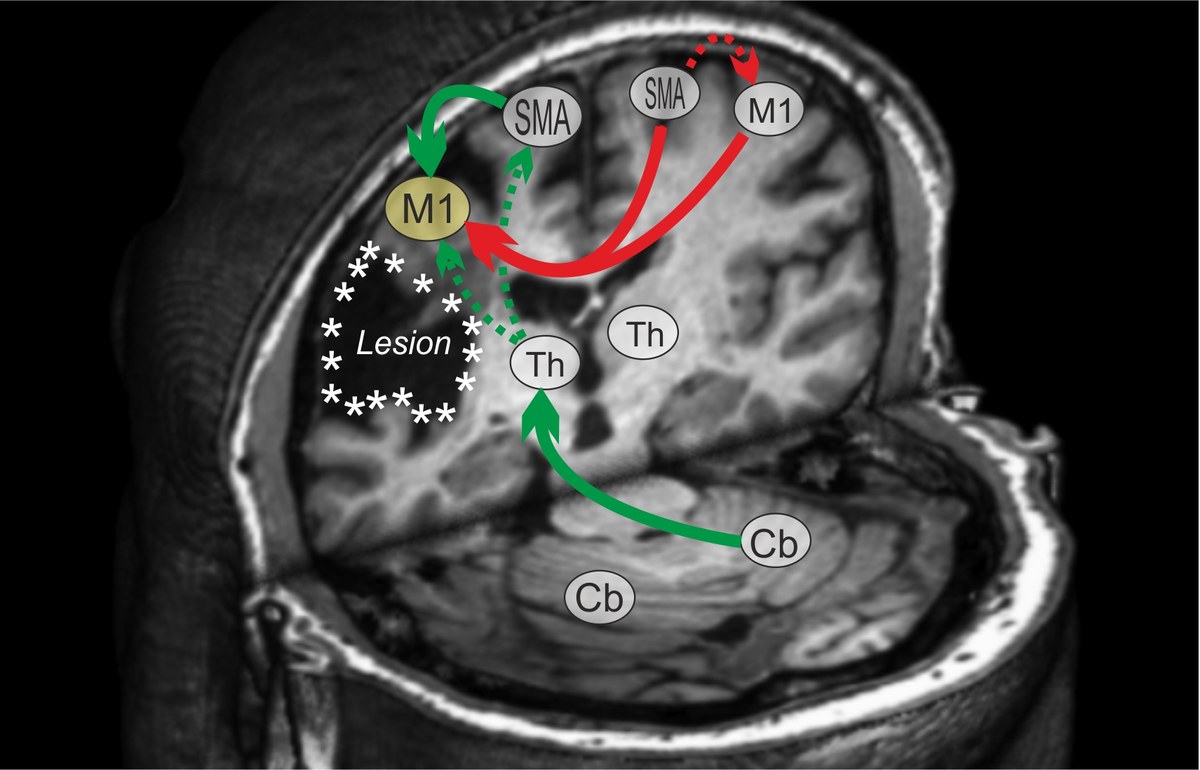

The scientific mission of the “Rehabilitation of Cognitive Impairments” group is to further our understanding of stroke-induced disturbances in brain network functions and the development of novel treatment strategies to promote recovery of function.

The aim is to elucidate which brain regions constitute key players in the process of functional reorganization, and how non-invasive brain stimulation may be used to “re-shape” neural networks to promote recovery of function. To achieve this, we combine neuroimaging (structural/functional MRI, electroencephalography) and computational neuroscience with behavioral, technical or pharmacological interventions that allow us to enhance neural plasticity and neurorehabilitation.